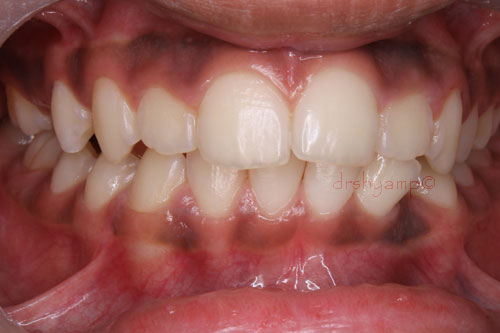

Removal of impacted canine